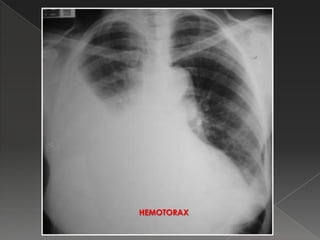

HEMOTORAX